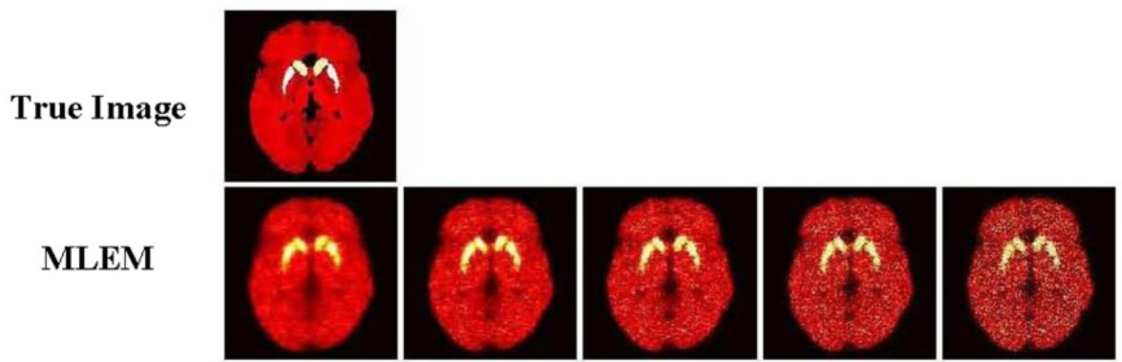

A C+Matlab-based PET simulation and reconstruction software, enabling realistic brain simulations, e.g. dynamic PiB PET imaging on the High Resolution Research Tomograph (HRRT).

• Statistical PET image reconstruction using 3D ordered-subset expectation maximization (OS-EM) algorithm